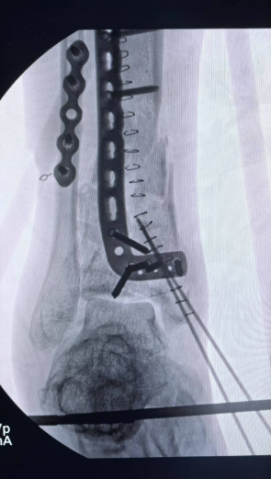

在手术过程中,王瑞国手术团队利用先进的影像学检查技术,精准定位每一处骨折线与碎骨片,为手术提供了详尽的蓝图。随后,团队创新性地采用双反牵引架进行牵引复位,为手术创造了良好的视野和操作空间。在专家的精湛技艺下,碎骨被逐一复位,关节面得到精心重建。最终,内固定钢板与外固定支架的联合应用,如同坚固的桥梁支架,确保了复位后的骨骼在愈合过程中的稳定性。